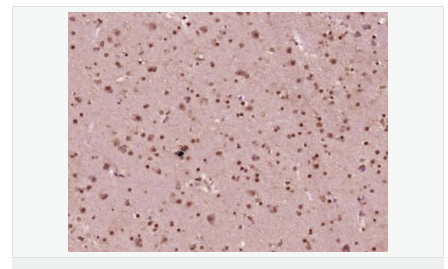

產(chǎn)品應(yīng)用WB=1:200-500 ELISA=1:5000-10000 IHC-P=1:100-500 IHC-F=1:100-500 IF=1:100-500 (石蠟切片需做抗原修復(fù))

細(xì)胞定位細(xì)胞核 細(xì)胞漿